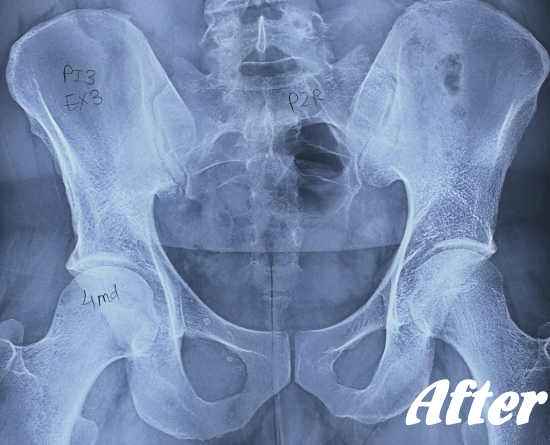

仙腸関節自体はごくわずかな動きしかありませんので、レントゲンやCT、MRIなどでは画像診断で判別することが難しいと言われています。

したがって、画像検査が難しいため、仙腸関節障害の診断は、症状経過と仙腸関節部の圧迫テストで診断されます。

HALOカイロプラクティック☆平和島整体院では、仙腸関節の動きやズレを回復させることを第一に考慮した施術を行っています。たとえ、足や肩の痛みやしびれが主訴であっても、仙腸関節を正しい状態に戻すことから施術を始めています。

仙腸関節、股関節、脊柱を特に集中して解剖学的に正しい位置へと戻す施術になります。HALOカイロプラクティック☆平和島整体院では、医療機関でも用いられているAKA療法も取り入れて施術しています。